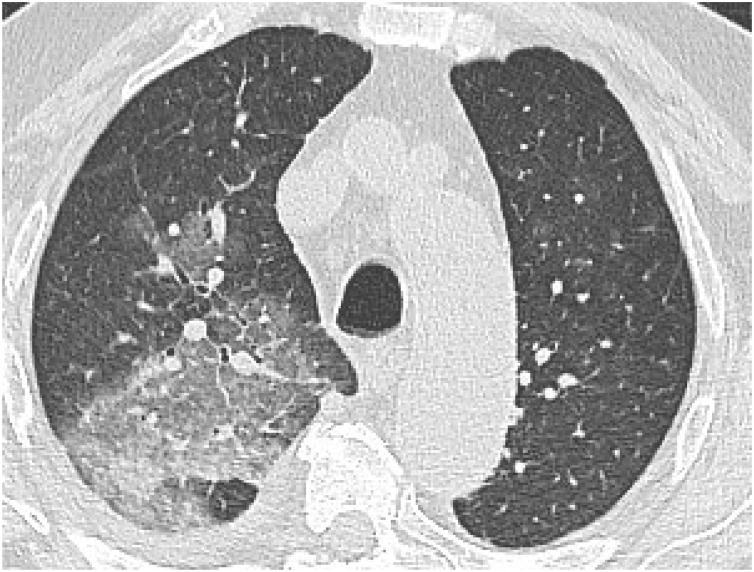

肺水肿:影像学表现及疾病机制的当前认识的图文综述

Pulmonary Edema: A Pictorial Review of Imaging Manifestations and Current Understanding of Mechanisms of Disease.

Pulmonary edema is a common clinical entity caused by the extravascular movement of fluid into the pulmonary interstitium and alveoli. The four physiologic categories of edema include hydrostatic pressure edema, permeability edema with and without diffuse alveolar damage (DAD), and mixed edema where there is both an increase in hydrostatic pressure and membrane permeability. As radiographic manifestations and etiologies are varied, an appreciation for both the common and uncommon manifestations and causes of pulmonary edema is essential for accurate diagnosis.

摘要

肺水肿是一种常见的临床病症,由液体向肺间质和肺泡的血管外移动所致。水肿的四种生理类型包括静水压性水肿、伴有或不伴有弥漫性肺泡损伤(DAD)的通透性水肿,以及静水压和膜通透性均增加的混合性水肿。由于影像学表现和病因各不相同,了解肺水肿的常见和不常见表现及病因对于准确诊断至关重要。